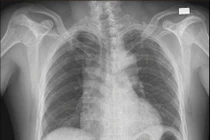

Bóc tách động mạch chủ trên chụp mạch - Ảnh BVCC

Bóc tách động mạch chủ là tình trạng cực kỳ nguy hiểm, xảy ra khi thành động mạch chủ – mạch máu lớn nhất của cơ thể bị rách và tách lớp, khiến dòng máu chảy sai đường.

Các chuyên gia phân tích, thành động mạch chủ gồm 3 lớp, lóc tách khi 3 lớp “vỏ” thành mạch không gắn kết mà tách khỏi nhau. Khởi đầu từ chỗ rách ở nội mạc gọi là điểm vào dòng máu chảy tách lớp áo giữa tạo nên "lòng giả".

Lòng giả phát triển dọc theo đường đi của động mạch chủ làm hẹp, tắc hoặc đứt các nhánh của động mạch chủ. Các nhánh khi bị đứt sẽ tạo điểm vào thứ phát, dòng máu sẽ chảy trong lòng giả từ điểm nguyên phát đến thứ phát ngăn cản hình thành huyết khối trong lòng giả.

Lóc tách động mạch chủ nếu liên quan đến vị trí của động mạch chủ lên thì được gọi là type A, nếu không liên quan gọi là type B. Khoảng 50% bệnh nhân lóc tách type A tử vong trong 48 giờ đầu, số còn lại cũng hầu như không có cơ hội sống sót nếu không được phẫu thuật.

Nguyên nhân tử vong là vỡ động mạch chủ vào màng tim, nhồi máu cơ tim cấp, hở van động mạch chủ cấp và tai biến mạch máu não. Type B trong phần lớn trường hợp không cần phẫu thuật.